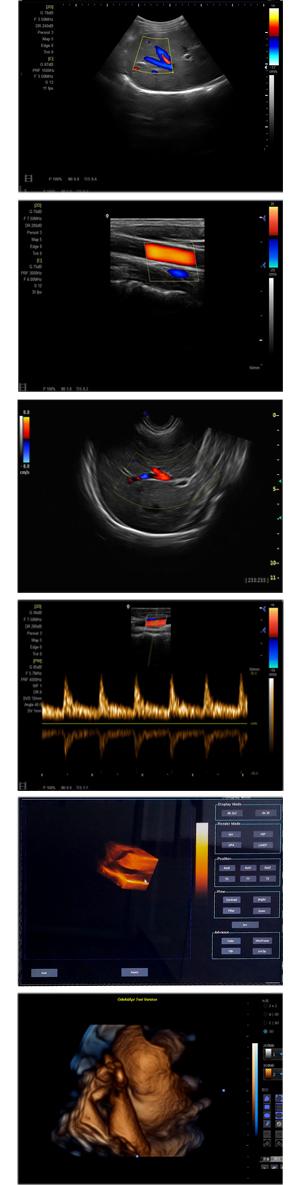

XF-7500型,秉承先鋒彩超技術(shù)之精華,擁有高雅大氣的獨(dú)特外型,為最新一代應(yīng)用型數(shù)字彩色多普勒診斷系統(tǒng),魅力與實(shí)力相融合??蓮V泛適用于腹部、婦產(chǎn)科、心臟、小器官、乳腺、肌骨及外周血管等諸多方面的診查,讓您在臨床超聲診斷應(yīng)用領(lǐng)域得心應(yīng)手,綻放異彩!

突破的成像技術(shù)

● 3D/ 4D成像技術(shù)/選配

● 應(yīng)用于腹部、腎臟、泌尿系統(tǒng)、產(chǎn)科、婦科、盆腔、大動(dòng)脈、肌肉組織、小器官、乳腺、心臟等

● 能量多普勒成像(PDI)

● 彩色血流量圖(CDE)

● 脈沖頻譜多普勒成像(PW)